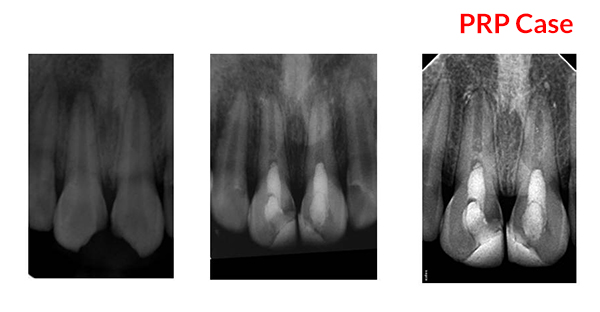

PRP Mediated REP in 21 with 18 months follow up

Bone healing, Apical PDL formed, Apex Closed, Calcific Bridge formed in 21.

Vitality Positive